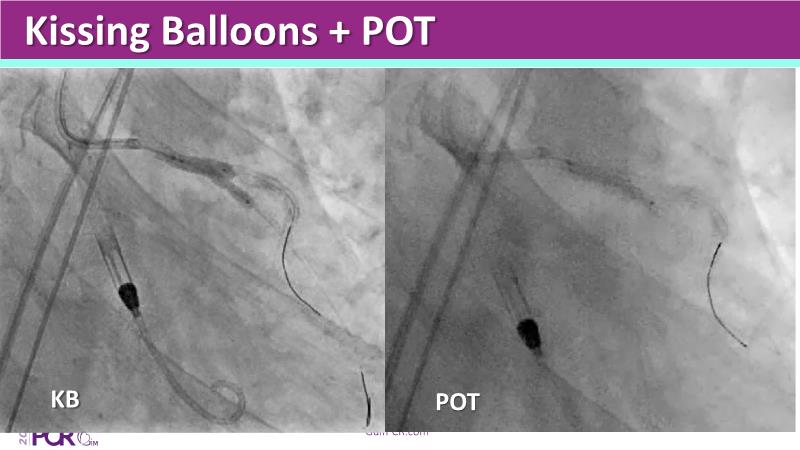

This session highlights the essential role of mechanical circulatory support (MCS) in managing high-risk PCI and AMI-related cardiogenic shock. Explore case-based discussions on device selection, hemodynamic impact, and evidence-based strategies to optimize outcomes in complex scenarios.